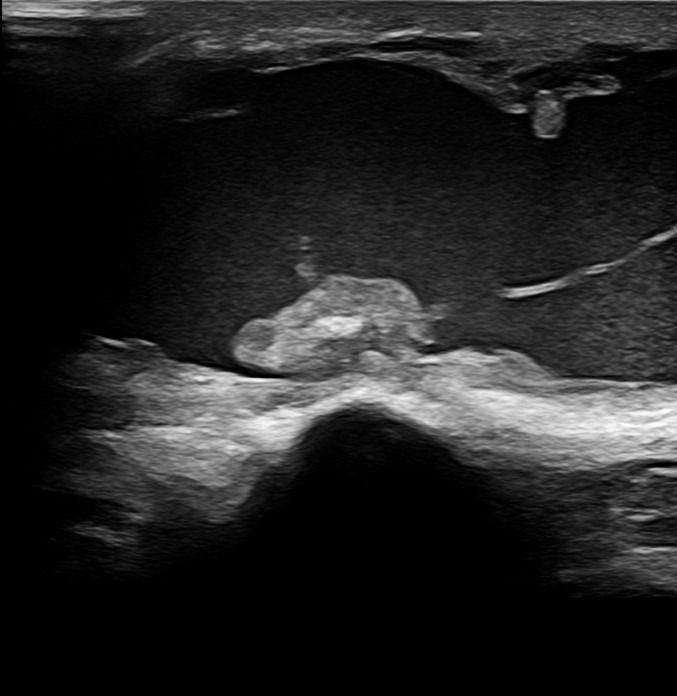

Elbow Joint

- Fluid collection in the elbow joint (i.e. hemarthrosis)

- Fluid collection in the bursa (i.e olecranon bursitis)